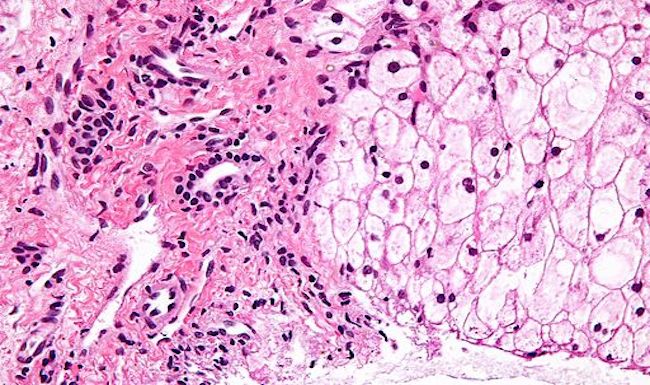

Activating Autophagy To Treat Metabolic Disease

Patients with glucose-6-phosphate deficiency (G6PD) could finally have a way to avoid fatty liver, enhancing their chances of living beyond early adulthood.